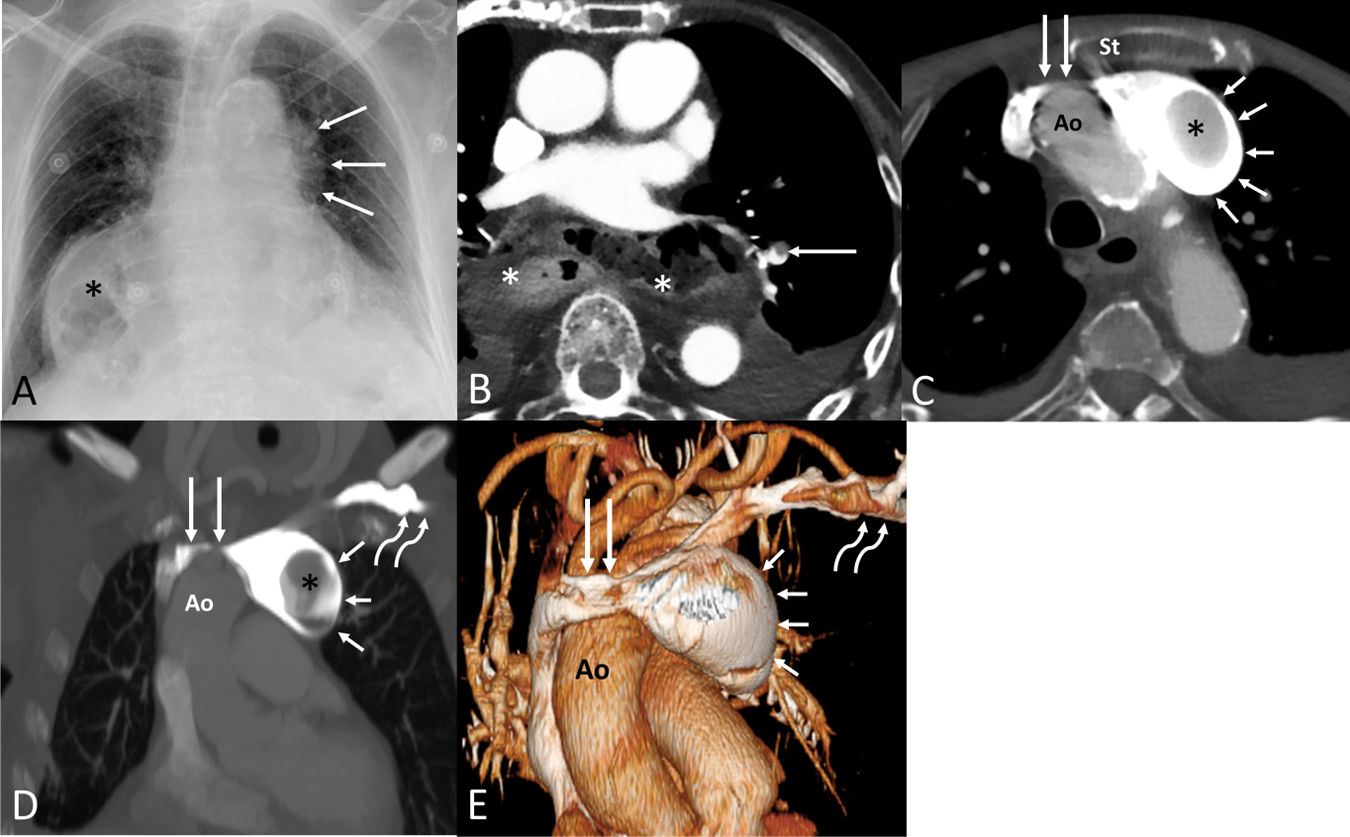

A 102-year-old patient presented to our hospital with shortness of breath. A chest radiograph showed an abnormal left mediastinal contour (Fig. 1A). A contrast-enhanced thoracic CT demonstrated a low-burden pulmonary embolism (Fig. 1B) as well as a narrowed aortosternal space resulting in a severe left innominate vein (LIV) compression and a large retrograde partially-thrombosed aneurysm of the LIV (Fig. 1C–E). Following consultation with the surgical team, it was decided to treat the patient conservatively (anticoagulant therapy). Isolated innominate vein aneurysms (IVAs) are very rare, with less than 36 cases reported in the literature [1]. The etiology of IVAs remains undetermined, although congenital malformations, trauma, vascular interventions (including intravascular devices), and inflammation/infection have been implicated. Most IVAs are incidentally detected on imaging, but some patients may experience symptoms due to rupture, thrombus formation or pulmonary embolism. The use of intravenous contrast is particularly important to avoid confusing an IVA with a solid mediastinal mass. Treatment options for IVAs include conventional open surgical repair and less invasive endovascular approaches, with the choice of technique guided by aneurysm morphology, symptomatology, and patient-specific risk factors. In our case, we speculate that the narrow aortosternal space may be the most plausible cause of chronic LIV stenosis and retrograde dilatation of the LIV with intra-aneurysmal thrombus formation.

(A) Anteroposterior chest radiograph shows an abnormal left mediastinal contour (arrows). Note a large hiatal hernia (asterisk). (B) Axial thoracic CT image shows a non-occlusive filling defect involving a segmental pulmonary artery (arrow); note the large hiatal hernia (asterisks). (C) Axial thoracic CT image demonstrates a narrowed left innominate vein (long arrows) running between the sternum (St) and the ascending aorta (Ao), a saccular aneurysm of the left innominate vein (short arrows), and a large filling defect within the aneurysm (asterisk). (D) Coronal thoracic CT image shows the compressed left innominate vein (long straight arrows) by the ascending aorta (Ao) and the retrograde aneurysmal dilatation of the left innominate vein (short arrows); note the intra-aneurysmal thrombus (asterisk) and the normal-looking left subclavian vein (curved arrows). (E) 3D reconstruction CT image shows the stenotic left innominate vein (long straight arrows) compressed by the ascending aorta (Ao), the retrograde dilatation of the left innominate vein (short arrows), and the normal-looking left subclavian vein (curved arrows).